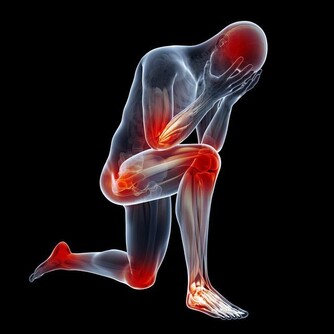

1、關節殘疾

體內的尿酸升高,超出人體承受的範圍,尿酸會形成結晶沉積在關節、皮膚、血管等地方,容易出現炎症。

痛風反復發作導致慢性痛風性關節炎,又會導致發作更加頻繁,間歇期縮短。疼痛逐漸加劇,受累的關節以膝、踝、肘關節多見,嚴重者可累及肩、髖、脊柱,很容易誘發關節的破壞與畸形,導致關節殘疾。